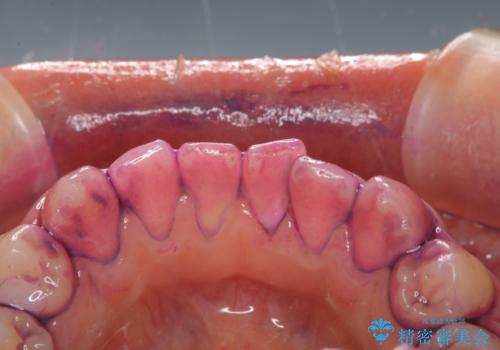

染め出し液を使ってプラークを染め出すことにより、普段の歯みがきで磨き残している場所を目で確かめることができます。

日々の歯磨きを上達するには、まずどこが磨けていないか認識することが大切です。